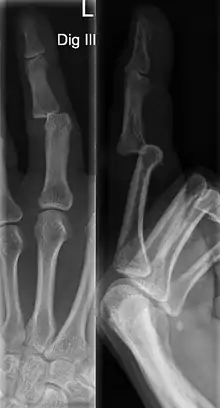

Dislocations can be categorised based on location and type. The finger can be split into three bones and two joints in an alternating order. From the fingertip to the knuckle, these are as follows; distal phalanx, distal inter-phalangeal (DIP) joint, middle phalanx, proximal inter-phalangeal (PIP) joint, and proximal phalanx. DIP dislocations are much less common than PIP dislocations,[2] due to the “stability provided by strong collateral ligaments, palmar plates, and tendinous insertions, as well as the short lever arm of the distal phalanx”.[7] Dislocations can be categorised based on the direction that the fingertip moves in relation to the knuckle, be it in the direction of the palm (volar dislocation), or the direction of the back of the hand (dorsal dislocation). Of the two, dorsal dislocations are more common.[3] If reduction has been attempted, an x-ray of the dislocation should appear concentric if successful.[2] However, if there is a fracture present, there will be a misalignment of the joint, which will be evident from the radiograph.[2] Bach suggests a referral to a hand surgeon if a misalignment is present.[2]

Fractures are instances where the bone's structural integrity has been compromised. This is indicated by midshaft pain, as well as visual midshaft angulation or rotation.[3] As with any skeletal injury, an x-ray can be conducted to verify the presence of a fracture.[1] The distal phalanx is especially vulnerable to avulsion fractures, where a fragment of bone is ripped off when the tendon separates from the phalanx.[1] Avulsion fractures are especially common following a first time dislocation.[1] These are especially concerning, as it may indicate a complete tear of the extensor digitorum tendon. If left untreated, this may lead to permanent DIP extensor lag (inability to fully straighten the finger).[8]